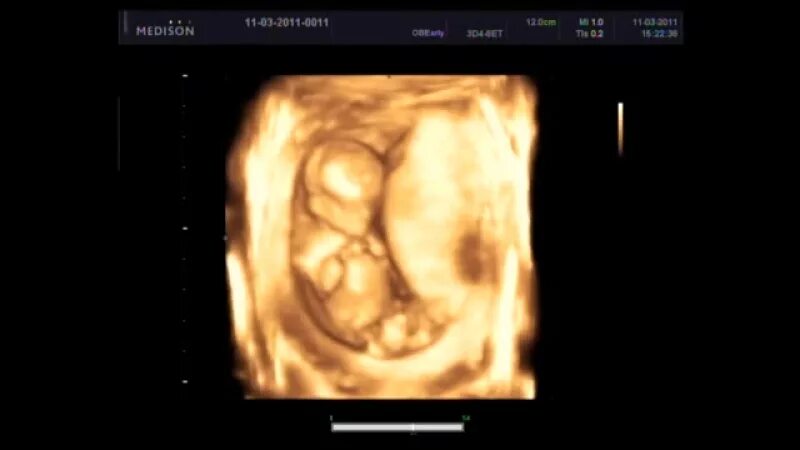

Недели третьего скрининга